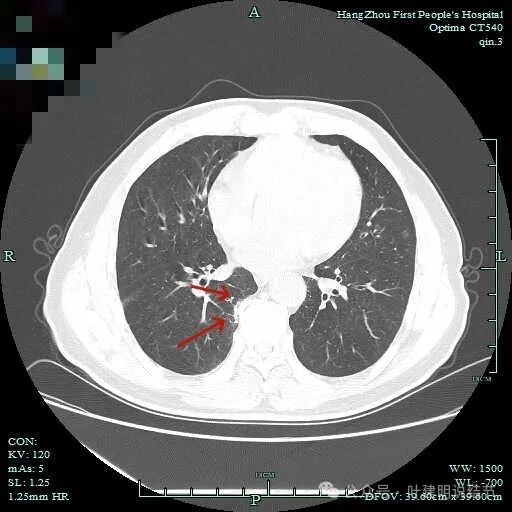

先看主病灶情况:

病灶出现,整体轮廓较清,胸膜略有牵拉。

密度不均匀,胸膜有轻微牵拉,边上有磨玻璃成分。

混合偏实性密度,瘤肺边界清,胸膜有牵拉。

表面不平,有小血管进入,整体轮廓与边界清。